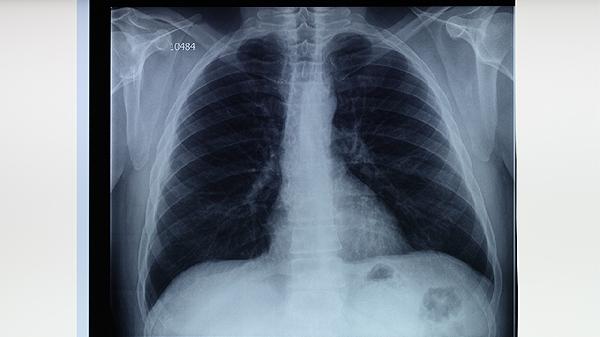

肺结核盗汗主要表现为夜间睡眠中大量出汗,常伴随低热、乏力等症状。盗汗可能与结核分枝杆菌感染引起的免疫反应、体温调节异常等因素有关,需结合痰涂片、胸部影像学等检查确诊。